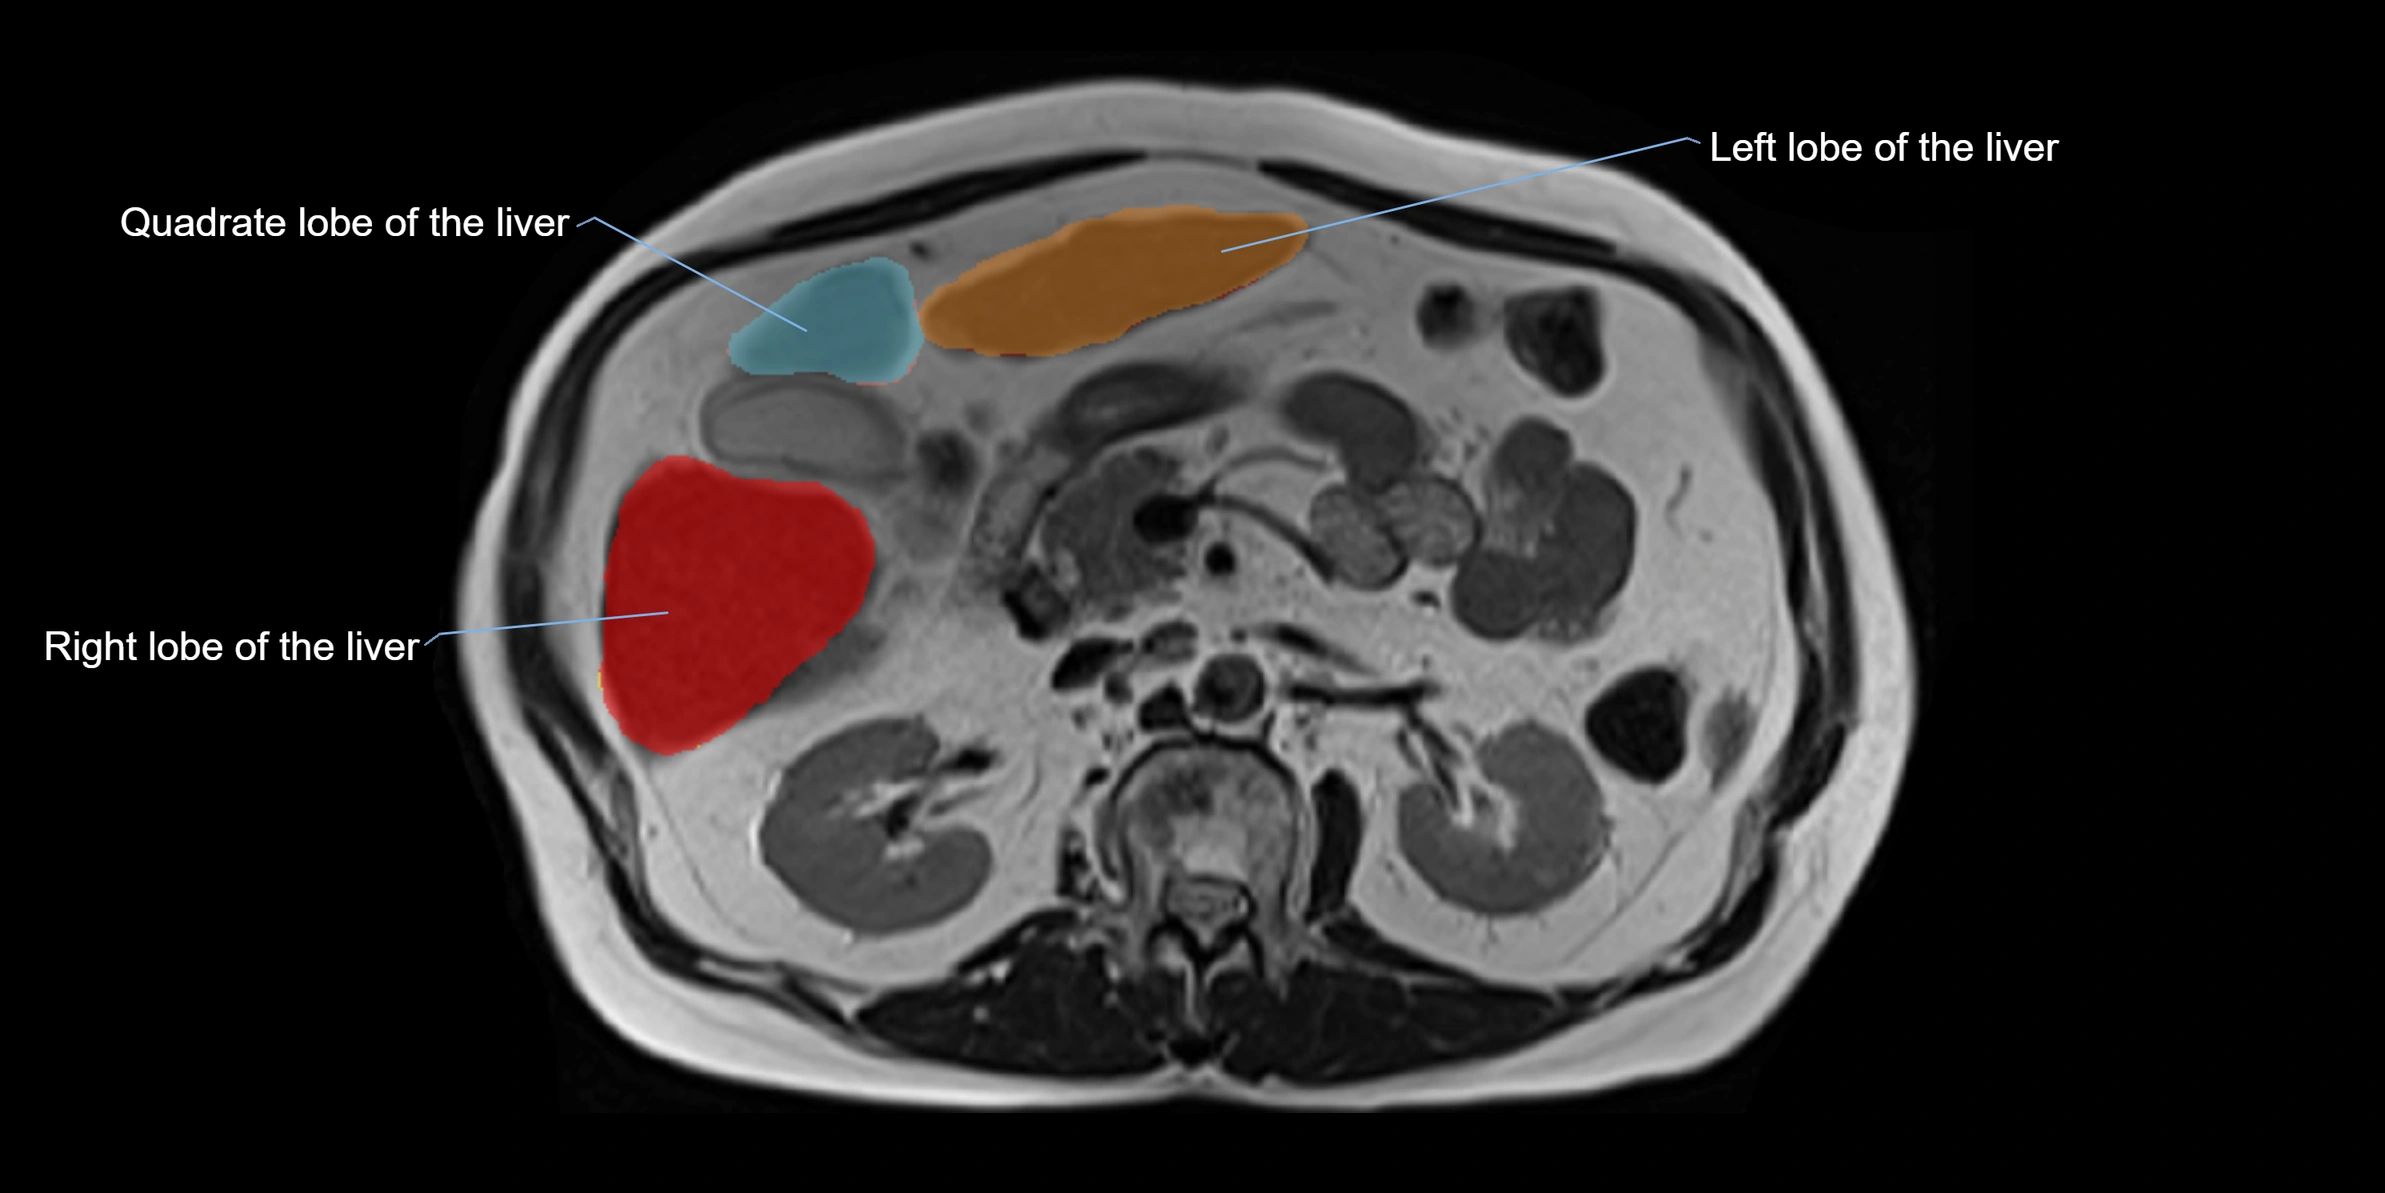

The caudate lobe of the liver is a distinct anatomical subdivision of the liver, designated as segment I in Couinaud’s classification. It lies on the posterior surface of the liver, between the fissure for the ligamentum venosum (left boundary) and the groove for the inferior vena cava (IVC) (right boundary). Superiorly, it is related to the posterior liver surface, and inferiorly it is separated from the left lobe by the porta hepatis.

This anatomical autonomy makes the caudate lobe especially significant in liver surgery, transplantation, and hepatic venous outflow obstruction syndromes (e.g., Budd–Chiari syndrome). Enlargement of the caudate lobe is a characteristic imaging feature in chronic liver disease and cirrhosis.